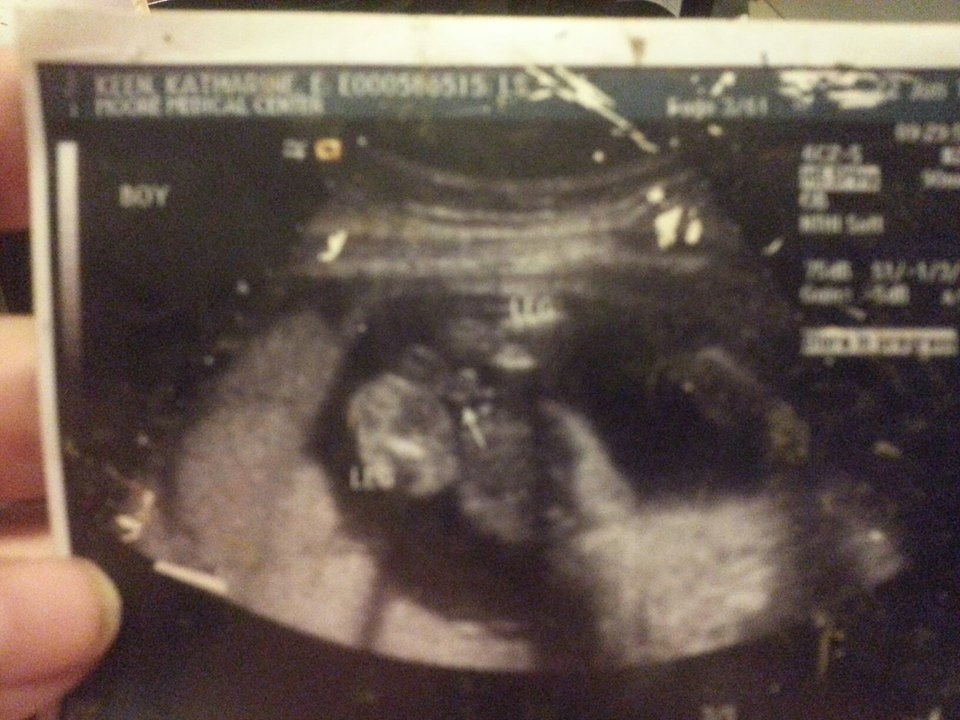

Here are some of the lost and found items: